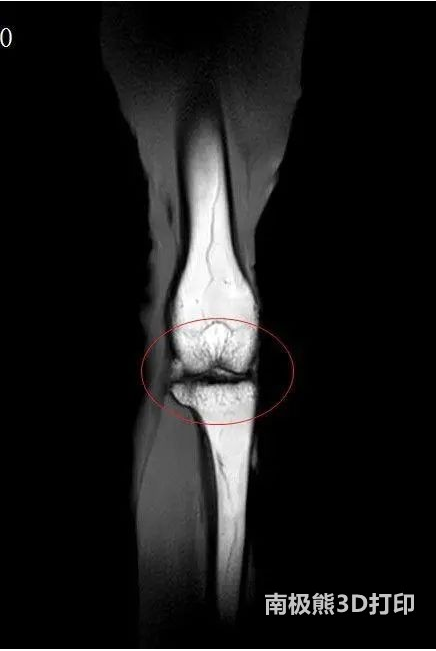

D打印骨軟骨支架修復老年關節軟骨損傷的論文近日在《Biofabrication(生物制造)》上發表,此項目由粵港澳大灣區科研人員共同研究,使老年人關節軟骨磨損、退化有望恢復如初。

關節軟骨在肢體活動中起重要作用,隨著年齡的增大,關節纖維彈性會減弱,關節液減少使軟骨變得干燥,因此人到一定年齡,就容易膝蓋痛、走路難,關節軟骨的老化和損失已成為降低老年人生活質量的一大“殺手”。關節軟骨分為軟骨層,過渡層和軟骨下骨層三層,每一層的韌度和硬度都不相同。傳統的臨床手段如關節鏡清理術、注射透明質酸或膠原蛋白都無法模擬人類軟骨的復雜結構,不同硬度的修復材料放在一起也容易產生滑移和脫落,療效很不理想。如何實現軟骨缺損組織的一體化修復?科研人員想到了生物3D打印技術。

來自香港大學、東莞理工學院、北京大學深圳醫院等單位的12位科研人員歷時2年,經過百余次反復實驗,從100余種原材料中進行篩選,發現以可降解聚酯、膠原蛋白水凝膠和生物陶瓷粉為原材料,用生物3D打印技術進行合成,可以模擬骨軟骨的多層結構。

“這些仿生材料就好比是‘墨水’,用打印機根據你缺損的形狀量身定做骨軟骨支架,植入缺損部位,同時加入生長因子和干細胞,幫助患者按支架的現狀長出軟骨結構。軟骨結構長成后,人工支架就會被人體吸收,患者的關節有望恢復如初。”本項目的科研人員王翀表示,“目前該支架可以模擬軟骨層和軟骨下骨層,未來還將研發出三層仿生支架。”

值得一提的是,此項研究攻克了界面強度難關,即可以讓結構、韌度不同的仿生軟骨層之間緊密結合,不會產生滑移,有很強的力學性能和穩定性。

據悉,目前此項技術要經過臨床前安全性測試和臨床試驗后,才可以投入臨床使用,此過程最快還需要5年。